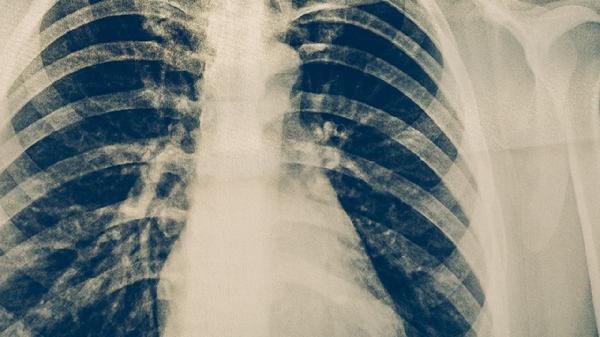

胸部X線能顯示肺結核典型病變如浸潤影、空洞或纖維化病灶。該檢查具有輻射量低、成像快速的特點,可作為初篩手段。但早期滲出性病變可能顯影不典型,需結合其他檢查綜合判斷。

胸部CT能清晰顯示微小病灶和縱隔淋巴結情況,對復雜病例的診斷價值較高。薄層掃描可發(fā)現早期粟粒性病變,增強掃描有助于鑒別腫瘤等疾病。檢查時需配合呼吸指令以保證圖像質量。